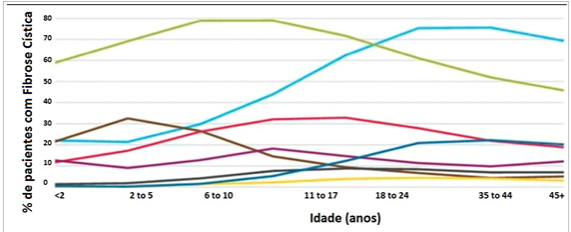

Os pacientes portadores de fibrose cística apresentam infecções respiratórias de repetição por patógenos variáveis durante a vida. A figura a seguir apresenta a distribuição dos patógenos em diferentes faixas etárias na fibrose cística.

Fonte: Pediatrics in Review 2014;35;194-203.

De acordo como os dados apresentados, na faixa etária de seis a dez anos, o micro-organismo que apresenta a maior porcentagem de infeção respiratória é: